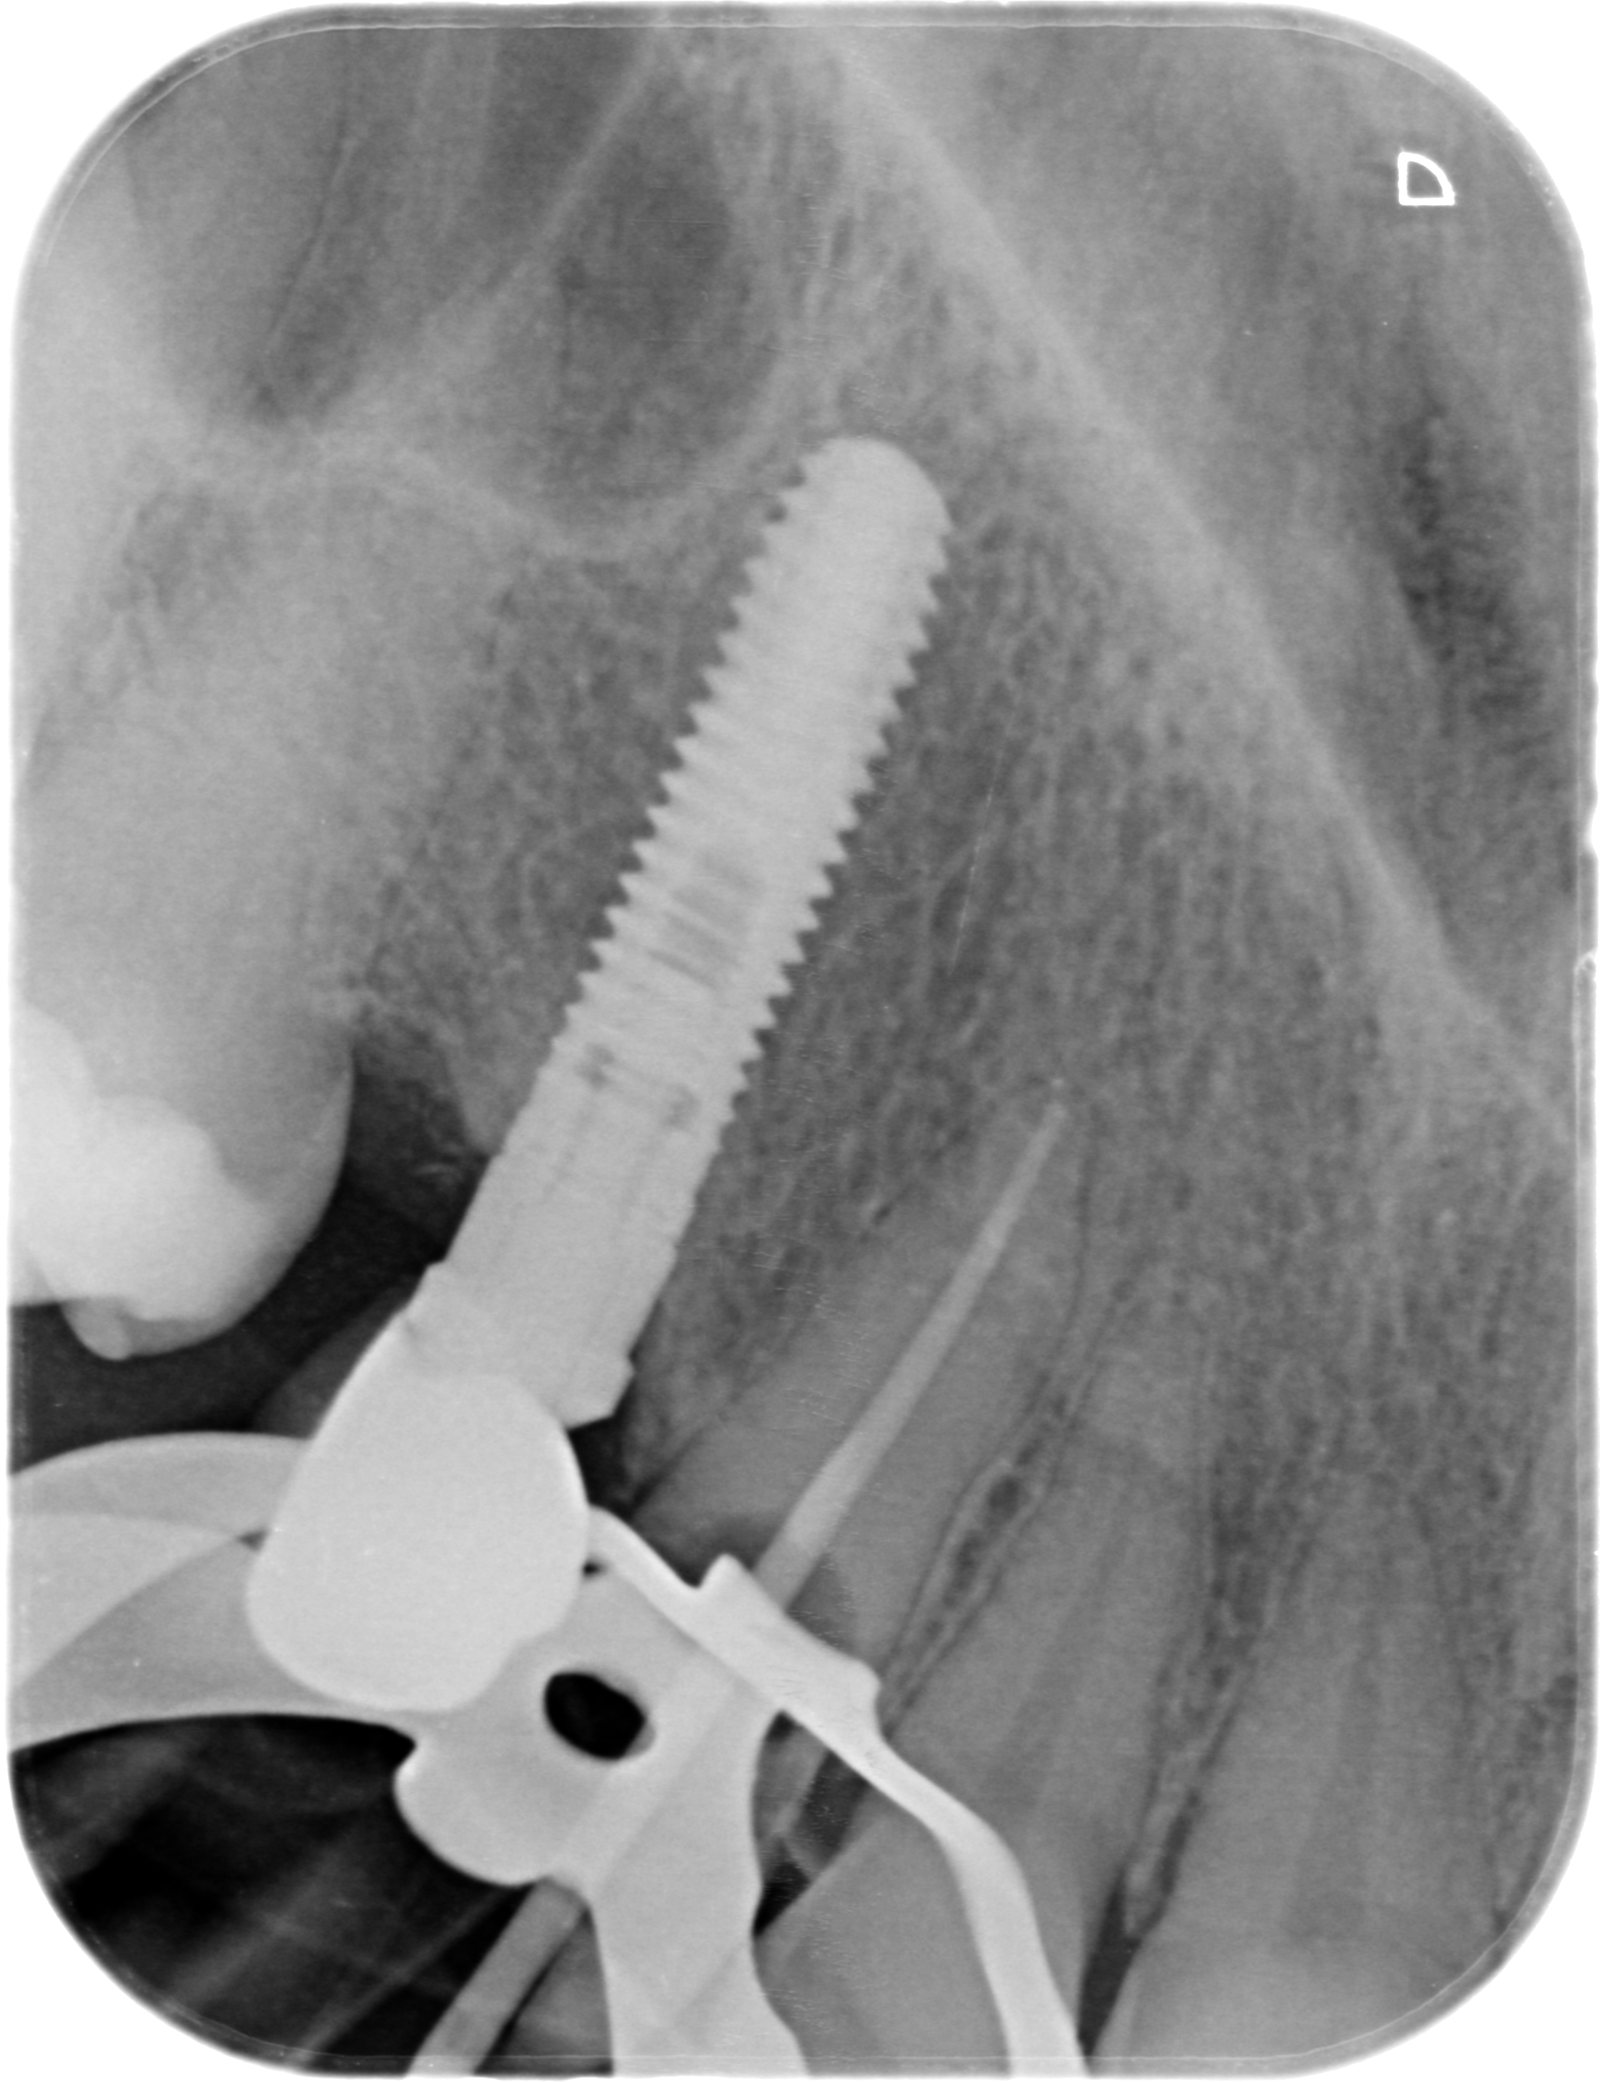

Implante en 14

Buenas tardes, adjunto la radiografía del implante del 14, colocado entre 2005 y 2009 según la paciente. Vino con la funda descementada y perforada por lo que queremos cambiarla. ¿Sabéis [...]